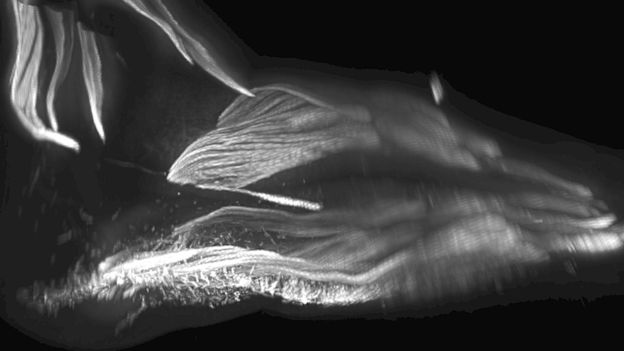

อ้างอิงจากผู้เขียนงานวิจัยชิ้นใหม่นี้ ที่ถูกตีพิมพ์ในวารสาร Development โดยทีมนักชีววิทยาประจำมหาวิทยาลัยฮาวเวิร์ด (Howard University) ของสหรัฐฯ จะเห็นได้ว่าเราไม่สามารถติดตามการก่อตัวของชิ้นส่วนร่างกายชั่วคราวเหล่านี้ในมนุษย์ด้วยรายละเอียดที่ดีสักเท่าไรนัก แต่ด้วยการใช้เทคนิคการถ่ายภาพสามมิติขั้นสูง ผู้เขียนกล่าวว่าพวกมันสามารถให้ภาพที่ชัดเจนที่สุดของการเติบโตของแขนขาของเราในช่วงต้น และยังพออีกว่าเป็นสิ่งที่ค่อนข้างแปลก

มีการสแกนภาพสามมิติของกล้ามเนื้อมือ ซึ่งได้จากทารกในครรภ์ 15 ราย พบว่าชุดกล้ามเนื้อดังกล่าวไม่มีอยู่ในสัตว์เลี้ยงลูกด้วยนมและมนุษย์วัยผู้ใหญ่ ทำให้สันนิษฐานได้ว่าเป็นลักษณะทางกายภาพชั่วคราว ที่ตกทอดมาจากบรรพบุรุษและยังคงหลงเหลือให้เห็น

ก่อนหน้านี้มีการใช้เทคนิคเดียวกันศึกษากล้ามเนื้อเท้าของทารกในครรภ์ และพบว่ามีการพัฒนากล้ามเนื้อชุดพิเศษขึ้นมาเช่นเดียวกับกล้ามเนื้อมือในช่วงหนึ่ง ก่อนที่จะสลายตัวไปเมื่ออายุครรภ์มากขึ้น